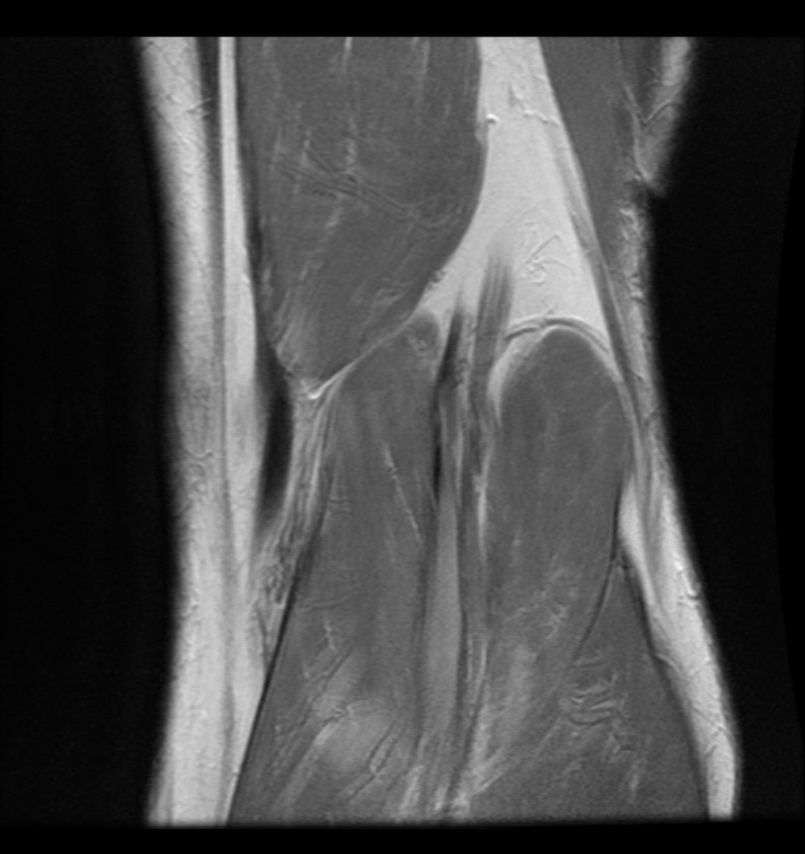

Today was a big day for my husband. Finally, he had his appointment with a orthopeadic surgeon to get the scoop on his torn meniscus. The doc seemed to favour continued physiotherapy for his 3 year-long battle with knee pain. I think my husband was hoping he would suggest that a quick fix of arthoscopic surgery would do the trick and after a bit of healing up he’d be back at it. Not so as ambiguity lingers on.

The doctor gave him a shot of cortisone to reduce inflammation to provide some temporary relief but what lies ahead? More physiotherapy it seems but now the therapist will have the benefit of the MRI of his knee. Can it be that my husband will never run another marathon? Sad, very sad . . .